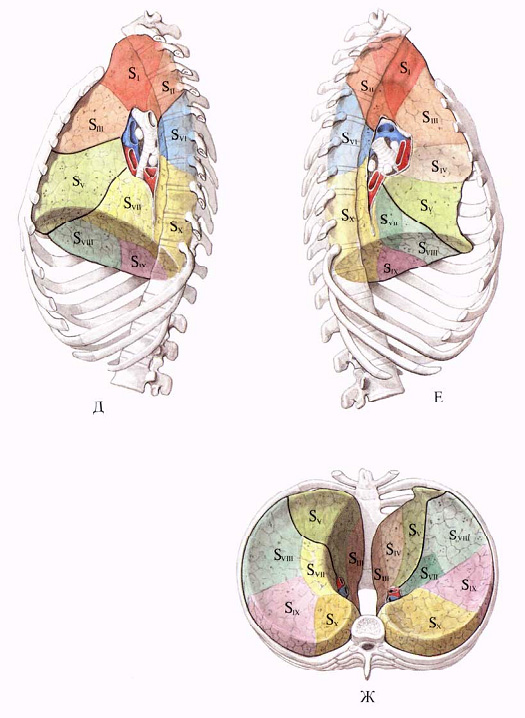

Анатомические изображения сегментов легких различных животных

Раздел: Другие животные